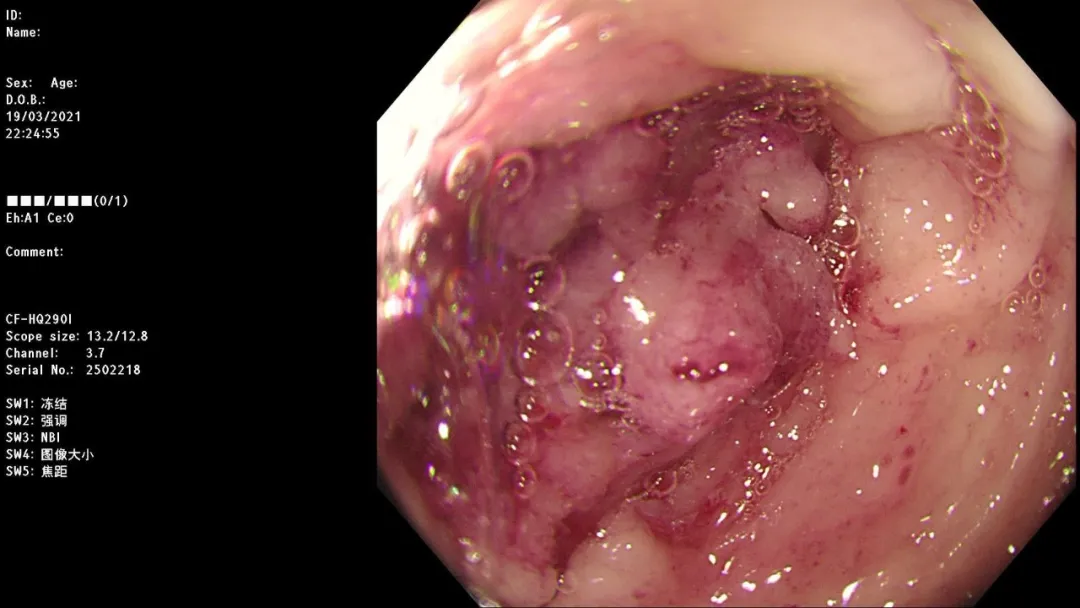

病例一:女,36岁,呕血2天,既往有乙肝病史,于南大一附院消化科就诊。

急诊胃镜示:食管距门齿32cm处可见一破口活动性出血,予套扎器套扎治疗,术后无活动性出血,检查诊断:食管静脉曲张破裂出血。